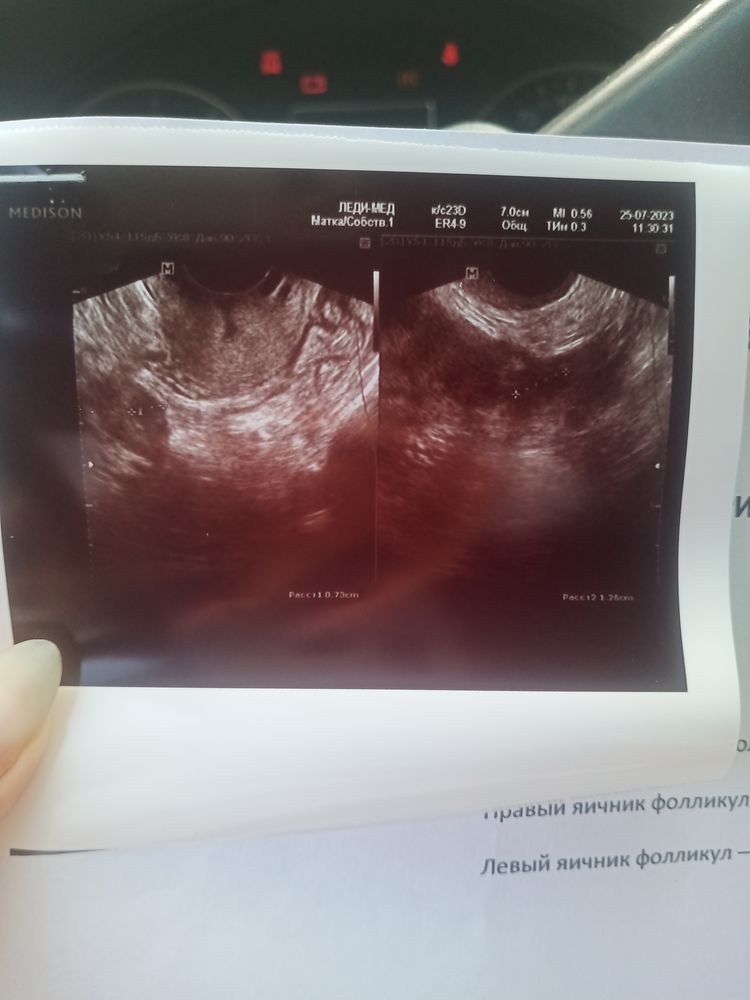

Фоликолометрия и фолликулы неправильной формы.

Вот так сказала врач. Что фолликулы не правильный формы. Что овуляции не будет скорее всего. И ничего не объяснила. Может у кого то было похожее. Это 11 дц. (Цикл 28-31 день. ) ничего не понятно. Сказала идти к врачу. Ну скинула я своей. Та сказала все нормально доминантный фолик есть.

Что значит не правильной формы ?